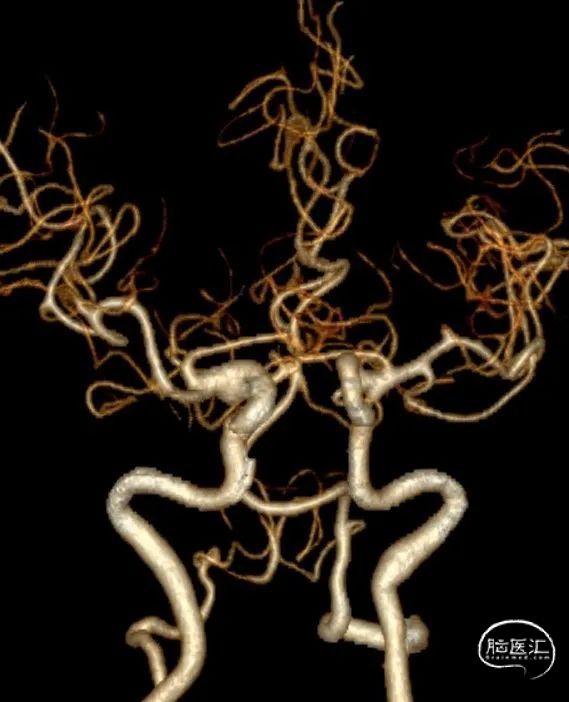

DSA结果:左侧P2段动脉瘤,约1mm*0.8 mm,颈宽约0.8mm,形态不规则。

术前影像DSA、DSA 3D

该病例为左侧大脑后动脉P2段微小宽颈动脉瘤,动脉瘤体直径仅0.9mm,载瘤动脉近端血管直径约1.7mm,远端血管直径约1.1mm,且双侧椎动脉均扭曲明显,但左侧后交通动脉粗大,考虑通过左侧后交通动脉为治疗路径,路途遥远,后交通的成角使得微导丝、微导管的操控存在一定难度;由于动脉瘤体小,因此微导管顺利进入动脉瘤腔内并保证安全是手术的关健点;支架微导管系统成功超选进入P3段远端也是手术成功的关键,对于支架的输送性和贴壁性要求极高。